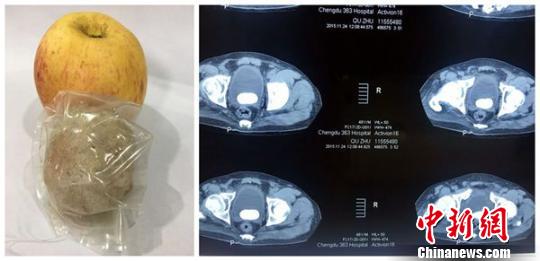

结石在该名体内的CT照片以及被取出后与苹果的对比?!×踅嗔妗∩?/span>

中新网成都12月17日电 (胡敏 刘洁伶)结石是人体泌尿系统常见的固体块状物,其形状大小不一,对人体健康的危害不容小觑。17日,记者从中航工业三六三医院获悉,该院在一例手术中,为一名男性患者取出了一块大如苹果的结石,这他消除了体内一大危害。

该名患者今年48岁,来自四川甘孜州,8年前因事故导致双下肢截瘫,近期突然出现血尿和双侧腰痛辗转至中航工业三六三医院就诊。当检查结果出来时,医生们都震惊了,该名患者膀胱内竟有直径达6CM的巨型结石。

患者在经过多次的详细检查和术前评估,三六三医院泌尿外科制定了完善的手术方案,采取膀胱切开取石术为患者取出结石。一般患者体内若出现1-2CM的结石便已是疼痛难忍,必须到院治疗,为何此患者至始至终竟未发现?